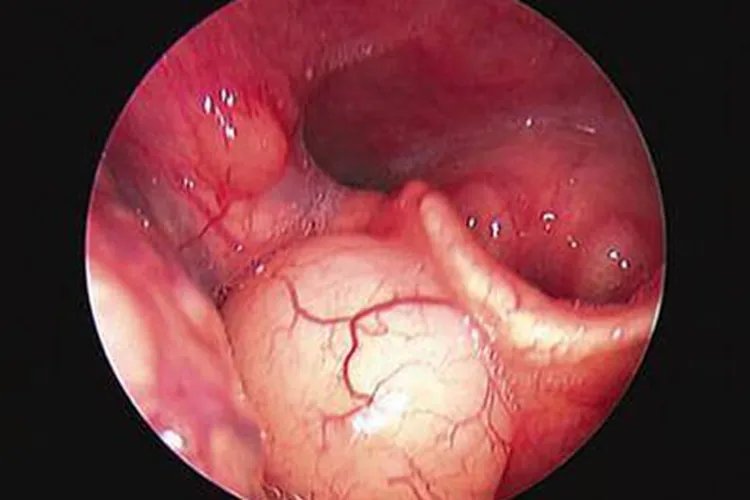

消化系统症状口服甲醛可导致消化道出现烧灼感、口腔黏膜糜烂、上腹部疼痛、有血性呕吐物,有时伴腹泻、便血等。严重者会发生食管和胃肠道黏膜糜烂、溃疡和穿孔,并可有休克、昏迷。